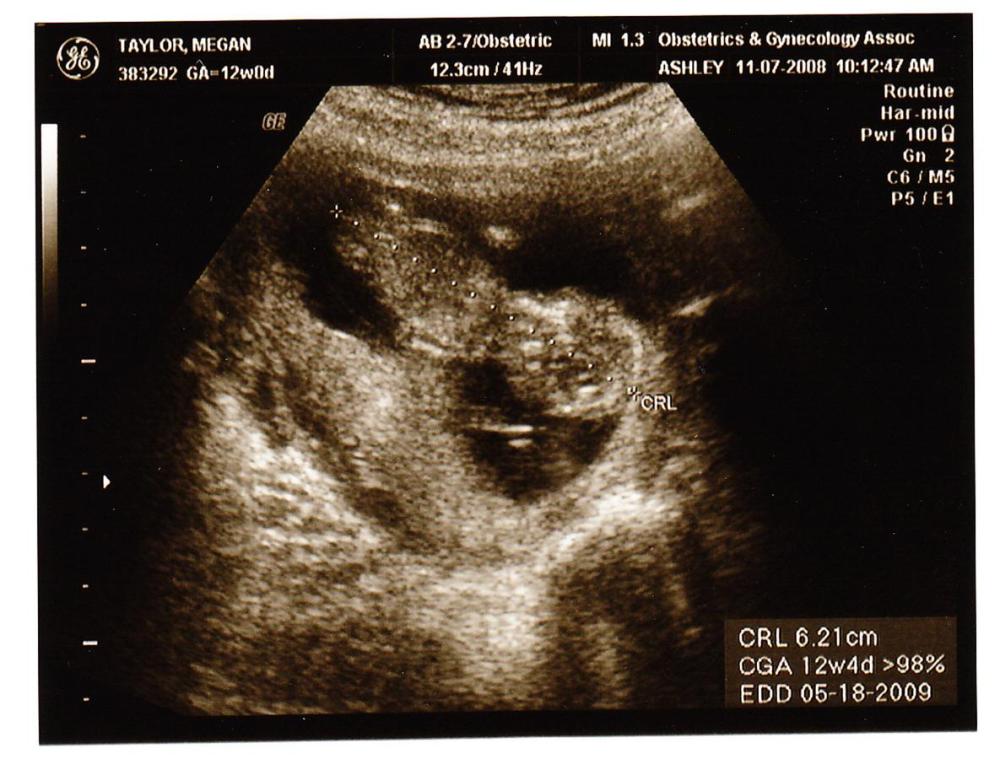

Our little baby is up to the monsterous size of 6.2 centimeters, which converts to about 2 1/2 inches… the dotted line runs the length of the baby and you can make out the large head – going to be in the gifted classes for sure…